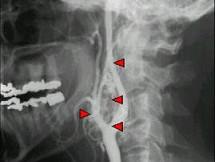

问题 50岁女性,颈部无痛性肿块,逐渐增大,听诊可闻及杂音,DSA检查如图所示,请选择最可能诊断 ( )

选项 A、颈动脉硬化 B、动静脉瘘 C、假性动脉瘤 D、颈动脉夹层 E、颈动脉体瘤

答案 E